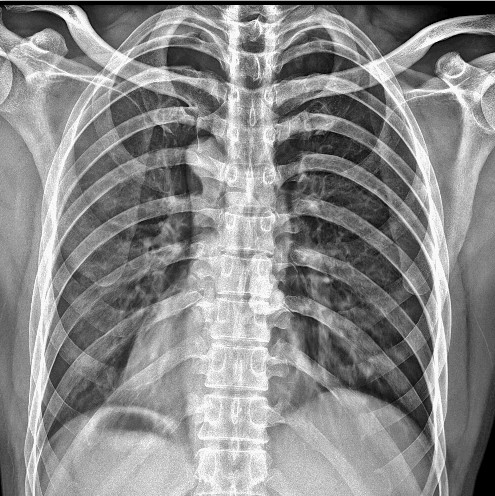

移动DR的临床应用包括胸部x光、肌肉骨骼成像、急诊创伤成像和新生儿/儿科成像等。例如,移动DR在紧急护理环境中非常有益,在紧急护理环境中,快速诊断和治疗决策至关重要,患者由于自身状况而无法转移到放射线室。此外,移动DR设备可用于对因医疗条件无法移动的患者进行床边成像。